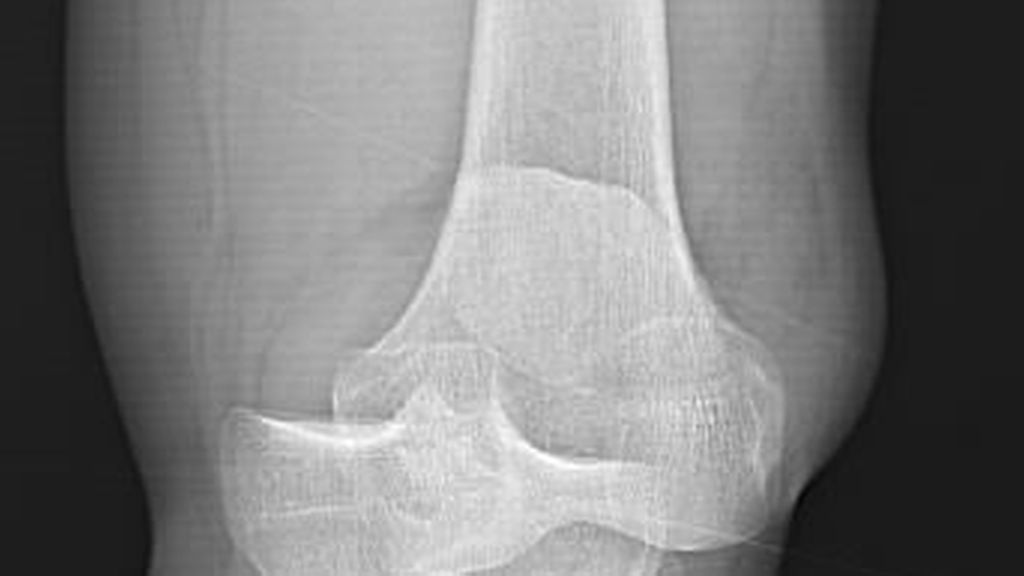

Knorpeldefekte im Knie können die Lebensqualität einschränken und langfristig zu Arthrose und der Notwendigkeit eines Gelenkersatzes führen. Es gibt diverse Behandlungstechniken, aber ...